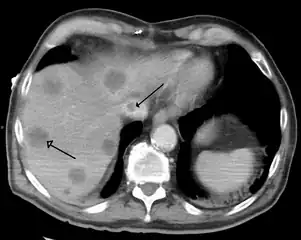

A previously undiagnosed liver disease may become evident first after autopsy. Following are gross pathology images: